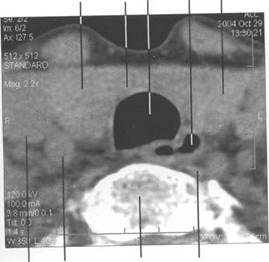

HU.